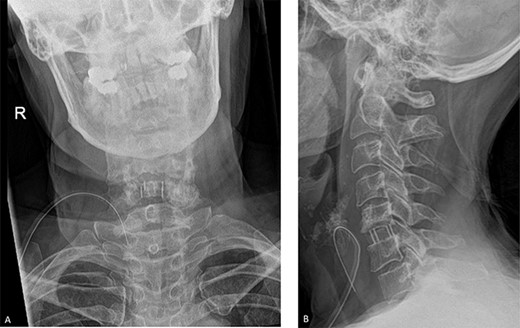

The patient underwent a C5/C6 anterior cervical discectomy and fusion (ACDF) (Fig. 2). Following the procedure, she had an uneventful recovery, and she was discharged the following day. At 3-month follow up, her symptoms had resolved entirely, and she resumed her normal work 5 weeks after surgery.

Post-operative radiographs. A. Anteroposterior view. B. Lateral view. The C5/C6 disc was identified using X-ray guidance and the vertebral bodies were distracted using Caspar pins. The endplates were prepared with a curette and the discectomy was performed. The posterior osteophytes were thinned with a matchstick drill and the posterior longitudinal ligament and posterior osteophytes were removed with Kerrison rongeurs.